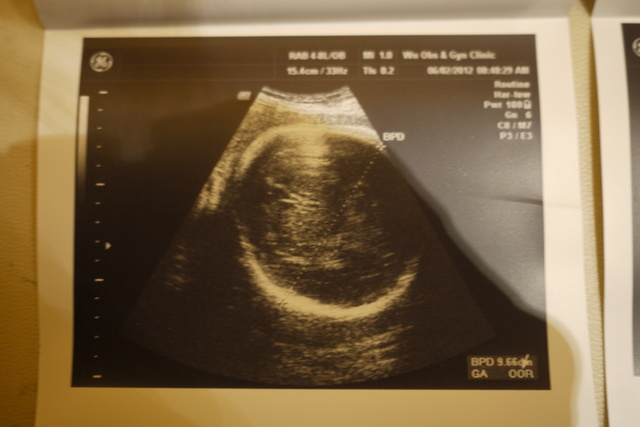

超音波照片有包括2D和3D的......

有部的特 ( 部特都是3D超音波 ).....有心、心跳、部、腿部的特....

小果可以量及身始......小果的一直都很大!!!!

例如在34.....小果的就是36大....腿骨36....身只有32大.....

是部的特.....

外面那圈白白的就是骨......